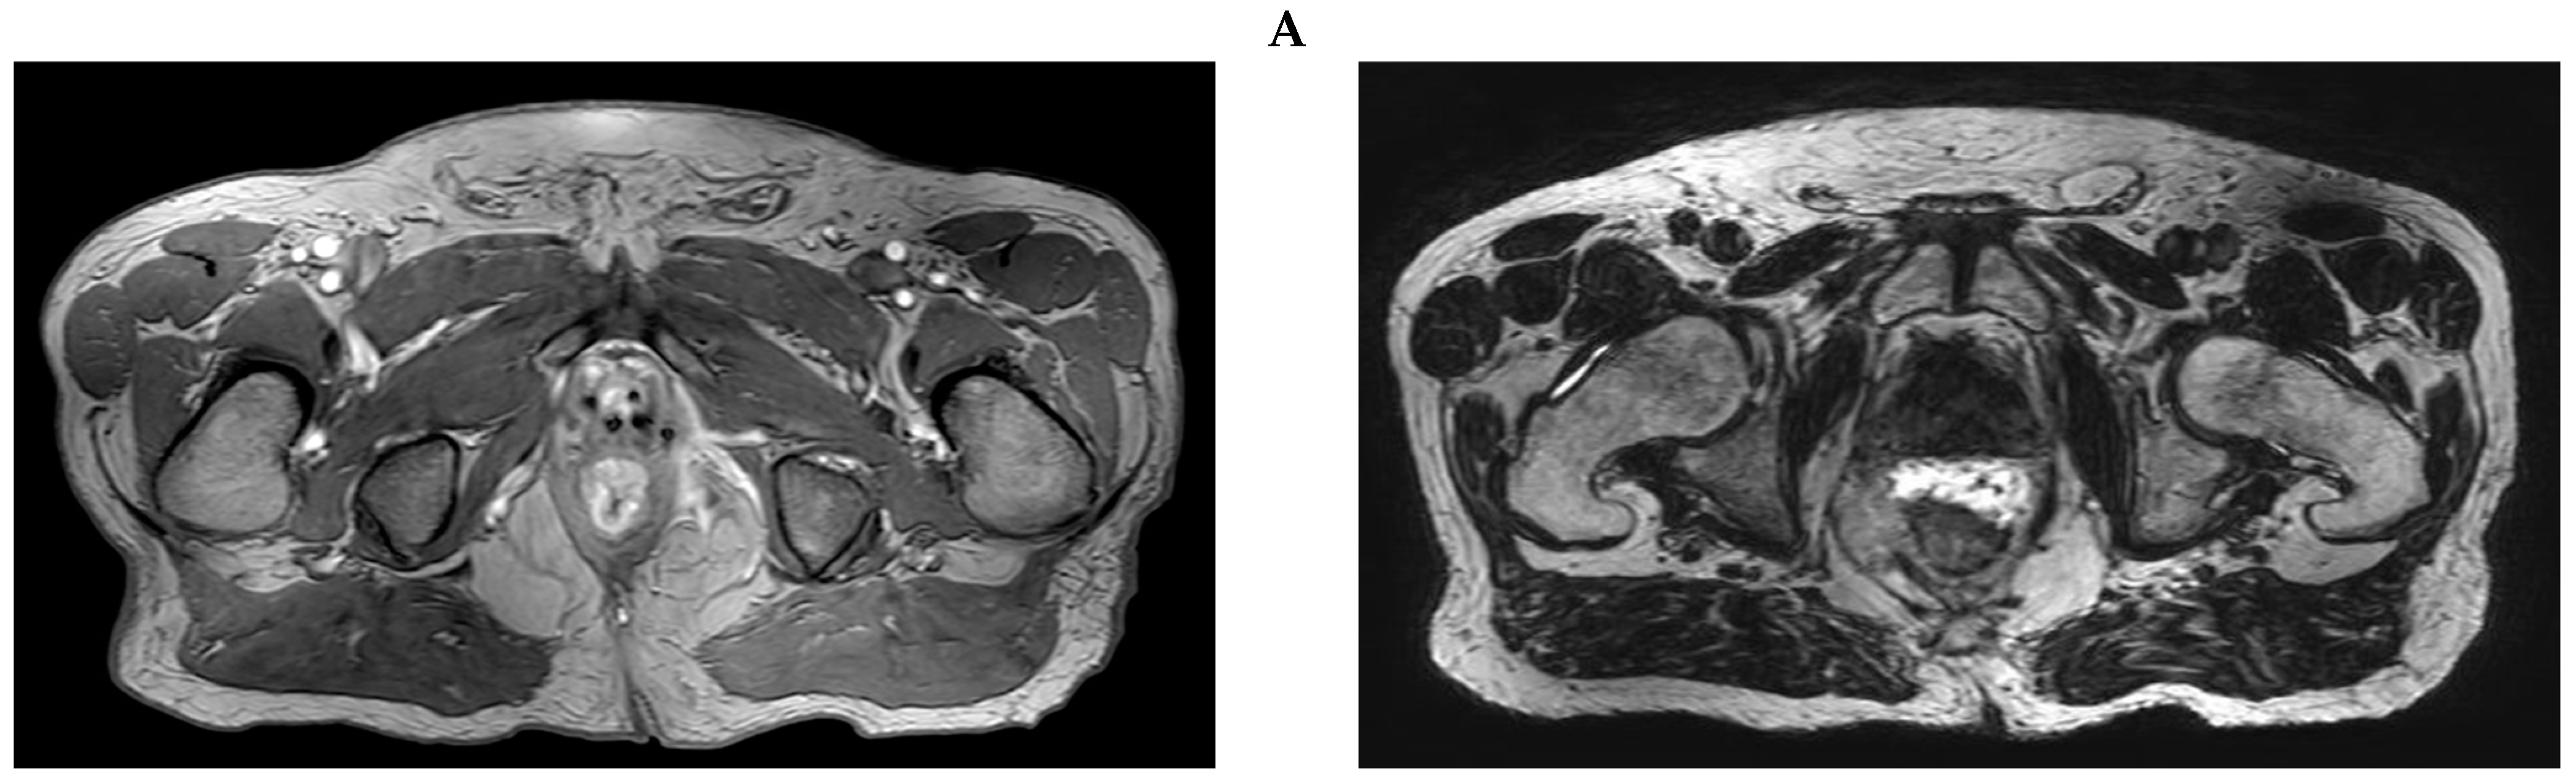

3.1. Case Report 1: Anal Squamous Cell Carcinoma

3.2. Case Report 2: Rectal Adenocarcinoma

| Anal | 2006: -LDR | 2018: -Anal canal + LNs 36–48 Gy/24 fx QD | -POD; liver -CR; local | NED | No POD | 2 mo; liver treated with SBRT | 48 mo |

| Rectal | 2013: -EBRT 81 Gy/45 fx | 2019: -Rectum + LNs 45 Gy/30 fx BID | CR | NED | No POD | No POD | 36 mo |